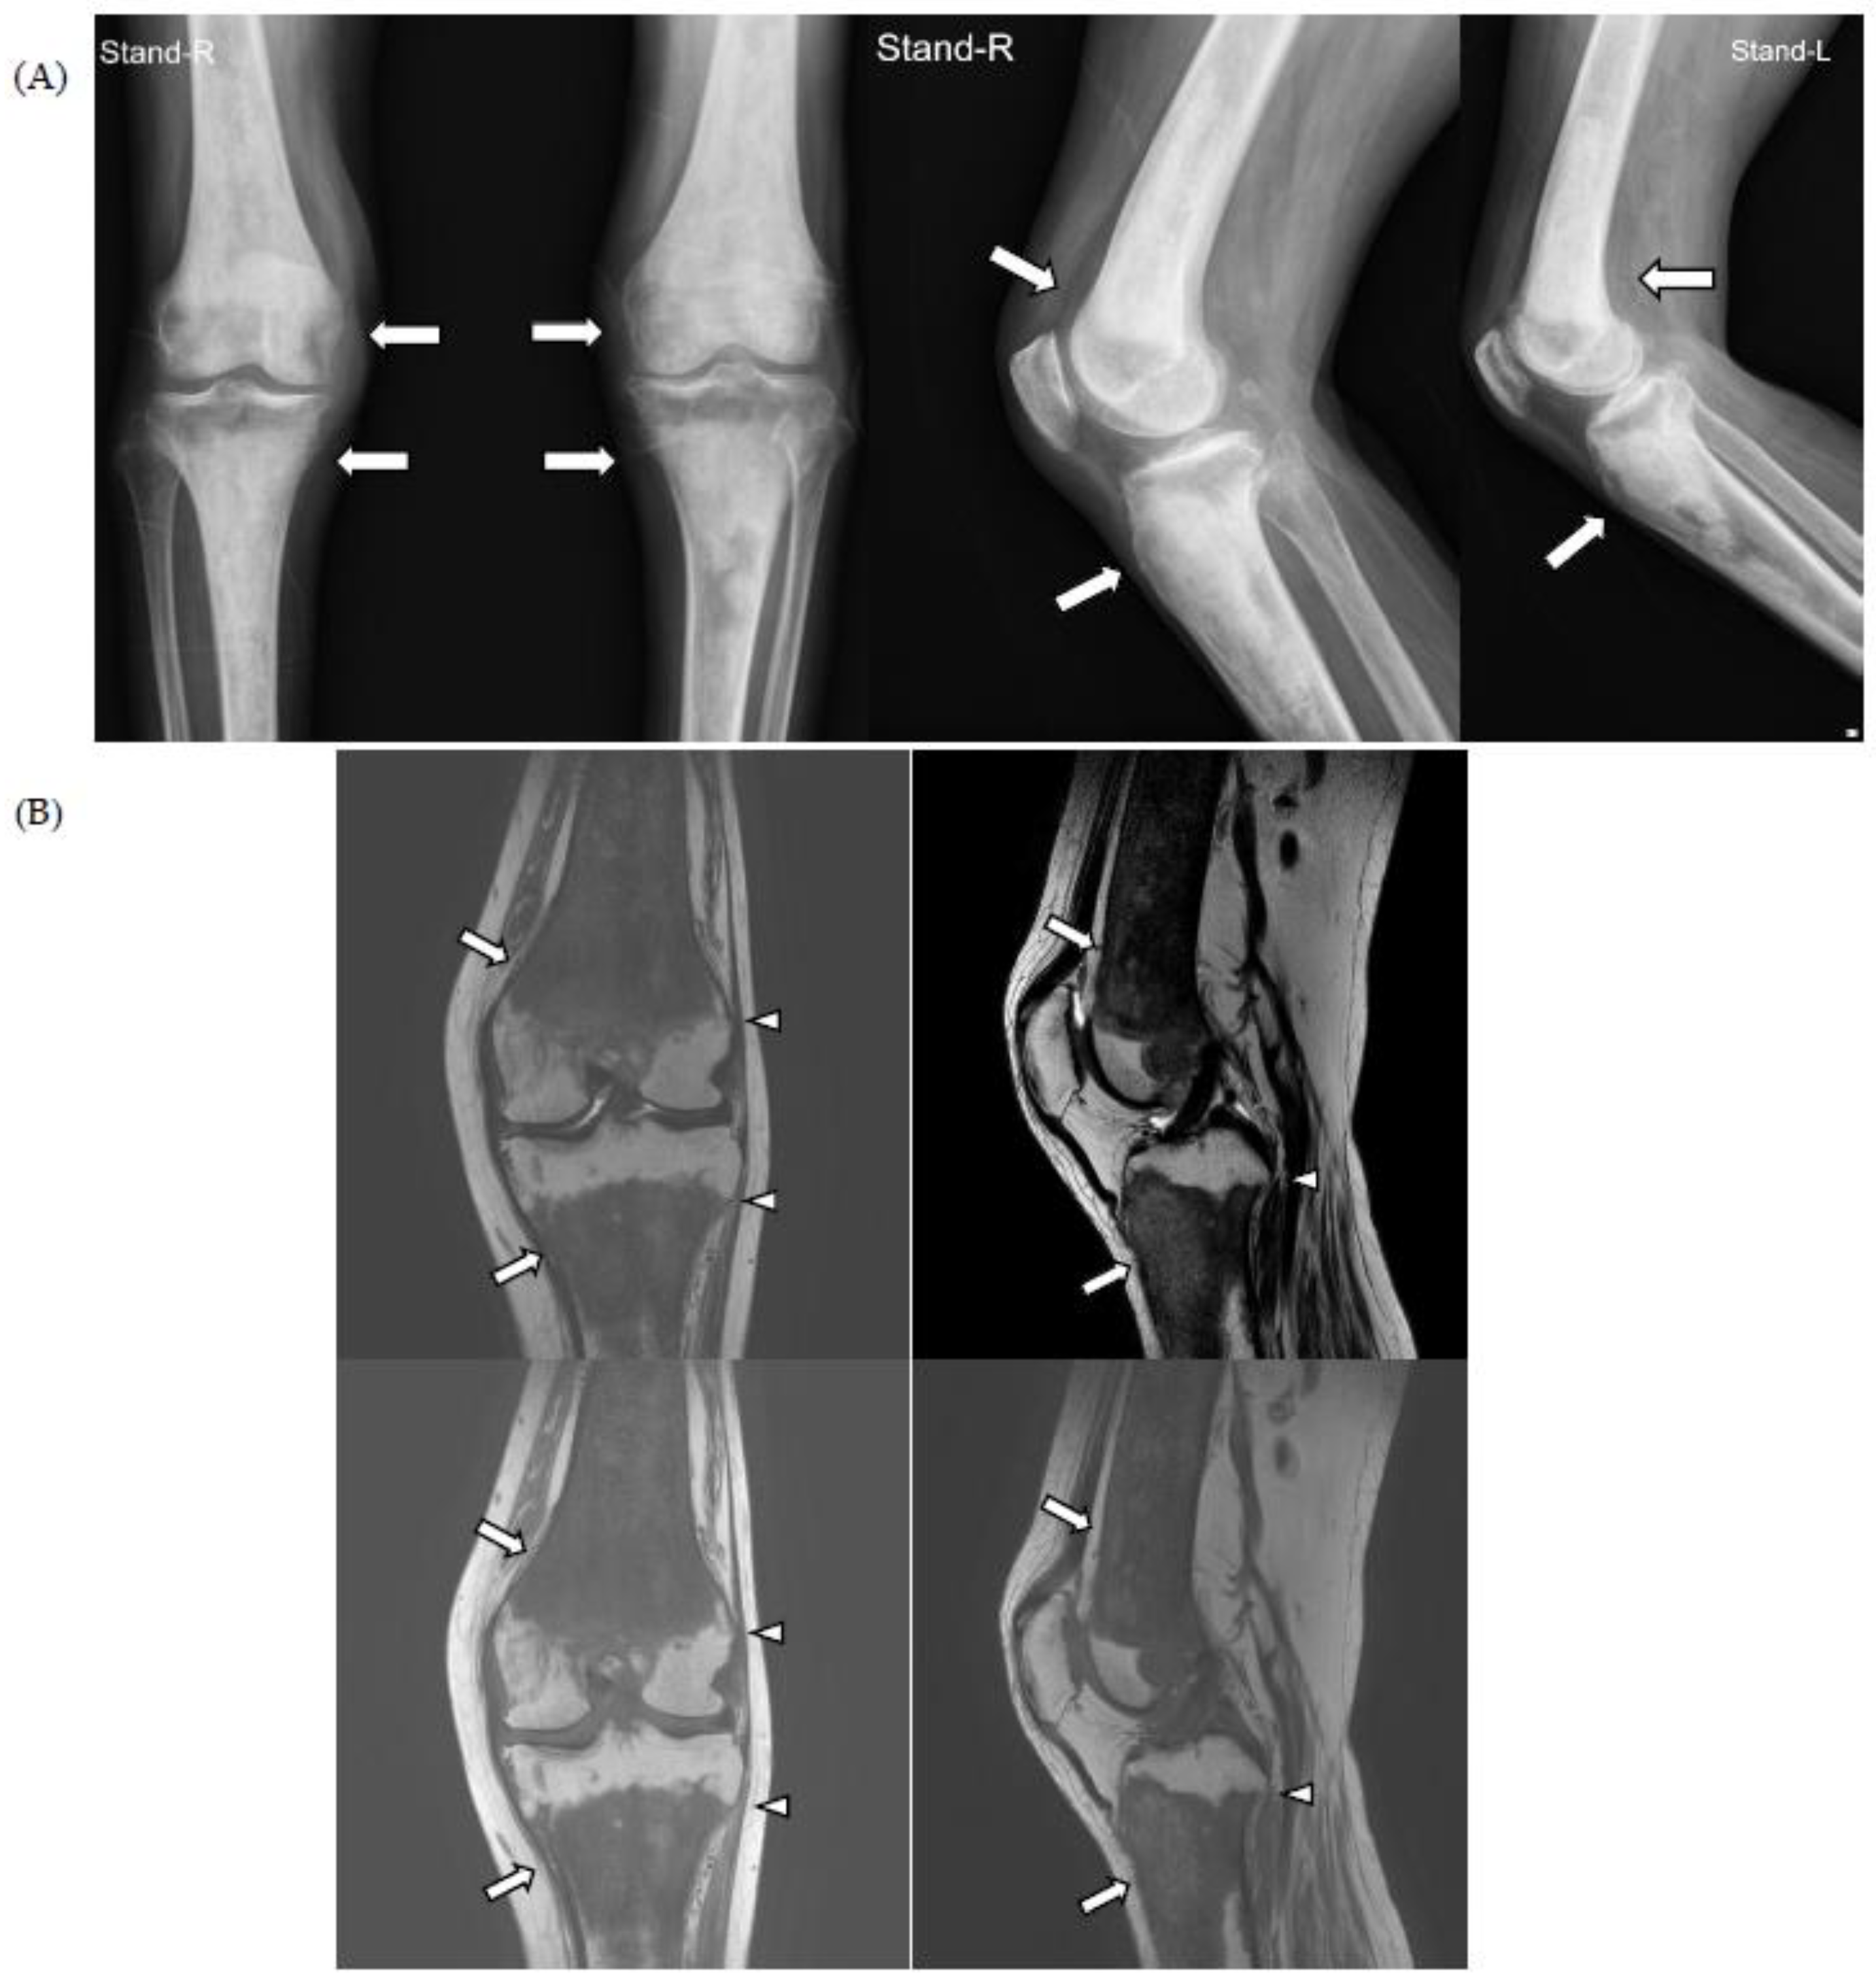

For knee pain and contracture, radiologic evaluation (simple radiography and magnetic resonance imaging (MRI)) of the knee joint was performed at another hospital, and the findings showed osteosclerotic lesions, which were thought to be bone metastases; therefore, the patient was referred to the hemato-oncology department of our hospital for cancer evaluation (Figure 1).

Figure 1.

On simple radiographs of both knee (A) and magnetic resonance imaging (MRI) of the left knee (B), there is characteristic symmetrical, bilateral cortical sclerosis affecting metaphysis and diaphysis of both the distal femur and proximal tibia (white arrows). Due to the disease progression, there is patch medullary sclerosis, with resultant loss of cortico-medullary differentiation. There is a spiculated margin to the epiphysis (white arrowheads), which shows that the epiphyseal surface is relatively preserved; ECD rarely affects epiphysis and axial bones.

The chest CT showed notable pericardial effusion with pericardial enhancement and pleural effusion with pleural enhancement (Figure 2). The abdominal CT showed fluid collection in both perirenal spaces and diffuse infiltration in both kidneys (Figure 3). Pericardial biopsy revealed chronic active inflammation with nonspecific findings. The PET/CT showed increased uptake in the sacrum, distal femur, proximal tibia, and spleen, with pericardial and pleural effusion (Figure 4). The simple radiography and MRI of the left knee showed patchy sclerotic changes in the medulla of the distal femur and proximal tibia (Figure 1).